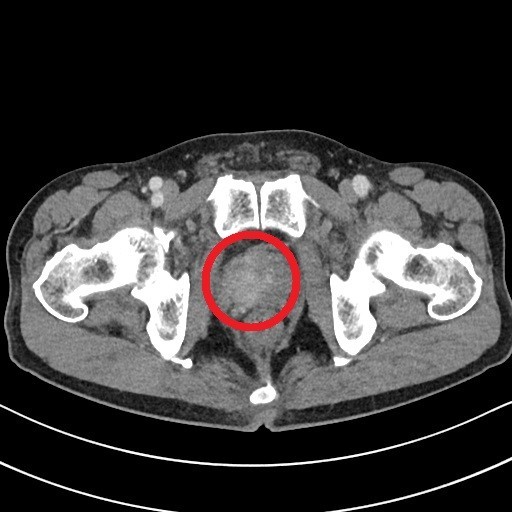

전립선암은 주로 전립선의 바깥쪽 부분인 말초대(Peripheral Zone)에서 발생합니다. 이 때문에 종양이 요도를 압박할 정도로 커지기 전까지는 증상이 나타나지 않는 경우가 많지만, 아래와 같은 비뇨기계 증상 및 전신 증상이 나타나기 시작하면 반드시 정밀 검사가 필요합니다.